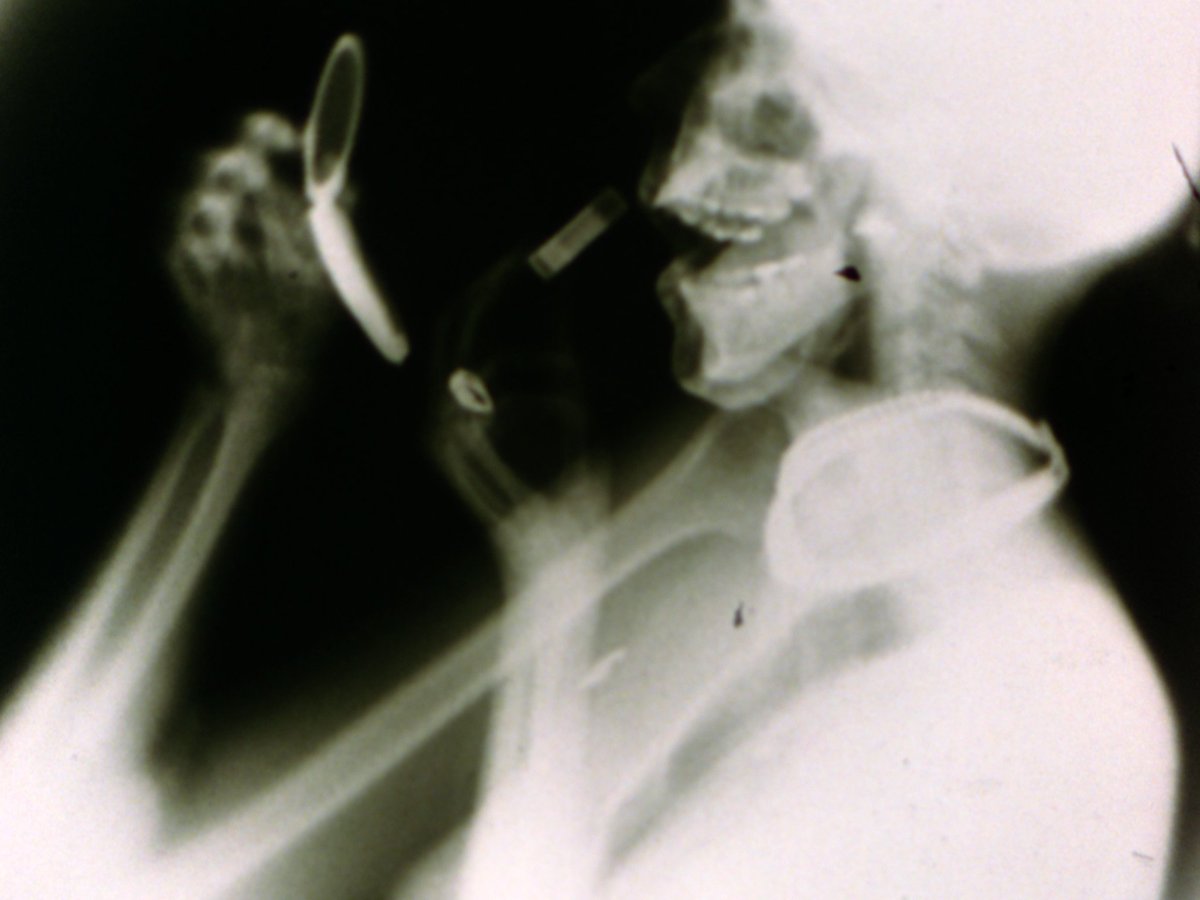

#WomenIlove #BarbaraHammer #Sanctus is een visueel gedicht dat gebaseerd is op wetenschappelijke röntgenbeelden van James Sibley Watson, arts en experimenteel filmmaker. 01.06 bit.ly/womenIlove